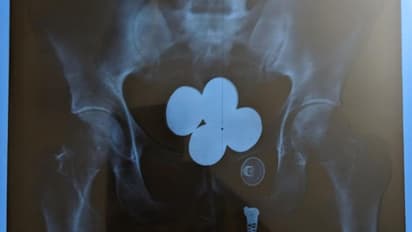

വിമാനത്താവളത്തിന് പുറത്തെത്തിയ ഉദയ് പ്രകാശിനെ പൊലീസ് കസ്റ്റഡിയിലെടുത്തു. തന്റെ പക്കല് സ്വര്ണ്ണമുണ്ടെന്ന കാര്യം ഉദയ് എത്ര ചോദ്യം ചെയ്തിട്ടും സമ്മതിച്ചില്ല. പ്രതിയുടെ പക്കലുണ്ടായിരുന്ന ബാഗുകൾ പൊലീസ് പരിശോധിച്ചെങ്കിലും സ്വർണം കണ്ടെത്താനായില്ല. പിന്നീട് പൊലീസ് കസ്റ്റഡിയിൽ ഇയാളെ വിശദമായ വൈദ്യ പരിശോധനക്ക് വിധേയമാക്കി. മെഡിക്കൽ എക്സ് റേ പരിശോധനയിൽ ഉദയുടെ വയറിനകത്ത് 4 കാപ്സ്യൂളുകള് ദൃശ്യമായി. പിടിച്ചെടുത്ത ഈ സ്വര്ണ്ണം കോടതിയില് സമര്പ്പിക്കും. തുടരന്വേഷണത്തിനായി വിശദമായ റിപ്പോര്ട്ട് കസ്റ്റംസിനും സമര്പ്പിക്കുമെന്ന് ജില്ലാ പൊലീസ് മേധാവി അറിയിച്ചു.

ആകെ 58 ലക്ഷം രൂപ മൂല്യം വരുന്ന 24 കാരറ്റ് 957.2 ഗ്രാം സ്വര്ണ്ണമാണ് ഇയാളിൽ നിന്ന് പൊലീസ് കണ്ടെത്തിയത്. സംഭവത്തിന് പിന്നാലെ 30കാരനായ ഉദയ് പ്രകാശിന്റെ അറസ്റ്റും പൊലീസ് രേഖപ്പെടുത്തി. സ്വര്ണ്ണം മിശ്രിത രൂപത്തില് നാല് കാപ്സ്യൂളുകളാക്കി ശരീരത്തിനുള്ളില് ഒളിപ്പിച്ചാണ് ഇയാള് ഷാര്ജയില് നിന്നും കടത്തിയത്.